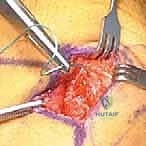

Intraoperative Masterclass: Step-by-Step Execution

Now, let's get down to business. We'll walk through the MPFL repair first, then the reconstruction.

Medial Patellofemoral Ligament (MPFL) Repair

This approach is typically reserved for acute, first-time dislocations with a clearly identifiable avulsion of the MPFL, often off the patella, and without significant attenuation.

2. Elevating Periosteum and Developing Tissue Planes

"Now, let's carefully elevate the soft tissues. Precision is key here to preserve the integrity of the retinaculum."

- Subperiosteal Incision: Make a vertical subperiosteal incision down to bone, approximately 1 to 1.5 cm lateral to the medial patellar border. This defines our working area on the patella.

- Periosteal Elevation: Using a small Cobb elevator or a Freer elevator, meticulously elevate the periosteum and all overlying soft tissues off the medial patella.

* Developing the Fatty Plane: With Metzenbaum or curved tenotomy scissors, carefully develop a tissue plane in the fatty layer between the retinaculum and the synovial joint capsule. This is a crucial step: we want to stay extra-articular.

> Surgical Warning: Avoid entering the joint space. This is an extra-articular procedure. Entering the joint increases the risk of arthrofibrosis and other complications.

3. MPFL Identification and Assessment

"Now, let's identify the MPFL itself. We need to assess its quality and suitability for repair."

- Digital Palpation: Place a finger into the extrasynovial tunnel you've just created. This tunnel lies just outside the synovium of the knee joint but is deep to the MPFL.

- Traction and Palpation: Apply gentle traction on the patellar end of the MPFL (if it's avulsed from the patella) with a Kocher clamp. Digitally palpate the MPFL on its inner surface, tracing it down to the medial epicondyle.

* Assessment: The MPFL should feel like a stout band of tissue originating from the medial epicondyle. If it's attenuated, frayed, or severely damaged, repair may not be sufficient, and reconstruction should be considered.

4. Patellar Preparation for Repair

"We need a good bed for healing on the patella."

- Decortication: Using a rongeur or a high-speed burr, perform superficial decortication of the exposed anterior medial patella. This creates a bleeding bony bed, optimizing healing of the advanced MPFL.